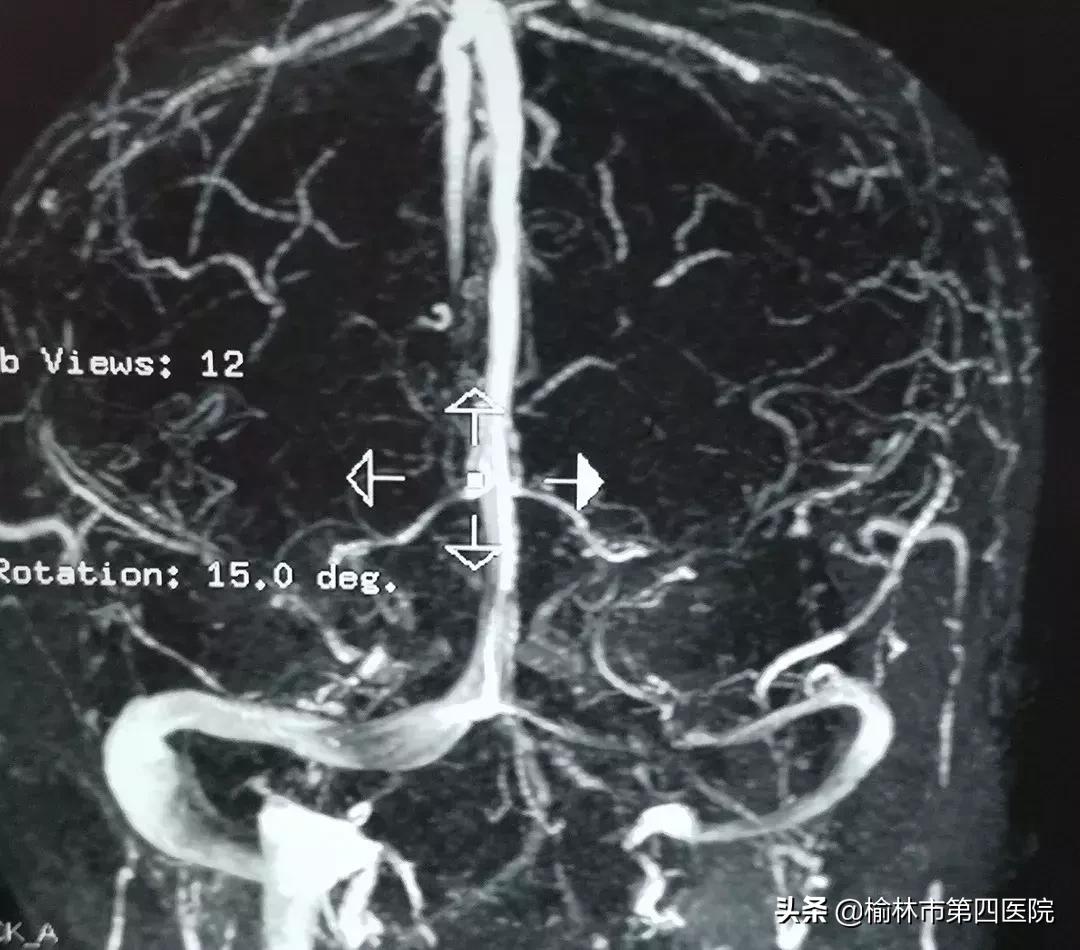

患者青年男性,5年前因病毒性脑炎治疗后持续头痛、头闷,症状时轻时重,一个月前“感冒”后出现头痛、头闷进行性加重,伴视物模糊,四处求医未果。后慕名就诊于榆林市星元医院,入院查体、各项化验、头颅MRI均未见明显异常,诊断性腰椎穿刺显示高颅压,眼底检查视乳头水肿。神经内一科常文利主任、李强主治医师凭借丰富的临床经验,考虑病因为颅内静脉系统疾病,遂行头颅MRV及全脑血管造影(DSA)示:左侧横窦长段重度狭窄。